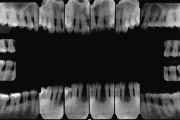

Krooniline parodontiit on mikroobide poolt põhjustatud hammaste tugikudede põletik, mille tulemusena tekib progresseeruv alveolaarluu (nähtav röntgenograamil) ja periodontaalligamendi destruktsioon, igemetaskute moodustumine, igeme retsessioon või mõlemad kahjustused kombineeritult. Loe edasi »

- luu destruktsioon (5)

- vertikaalne luukadu (2)

- horisontaalne luukadu (3)

- hamba kinnitussidemete kadu (3)